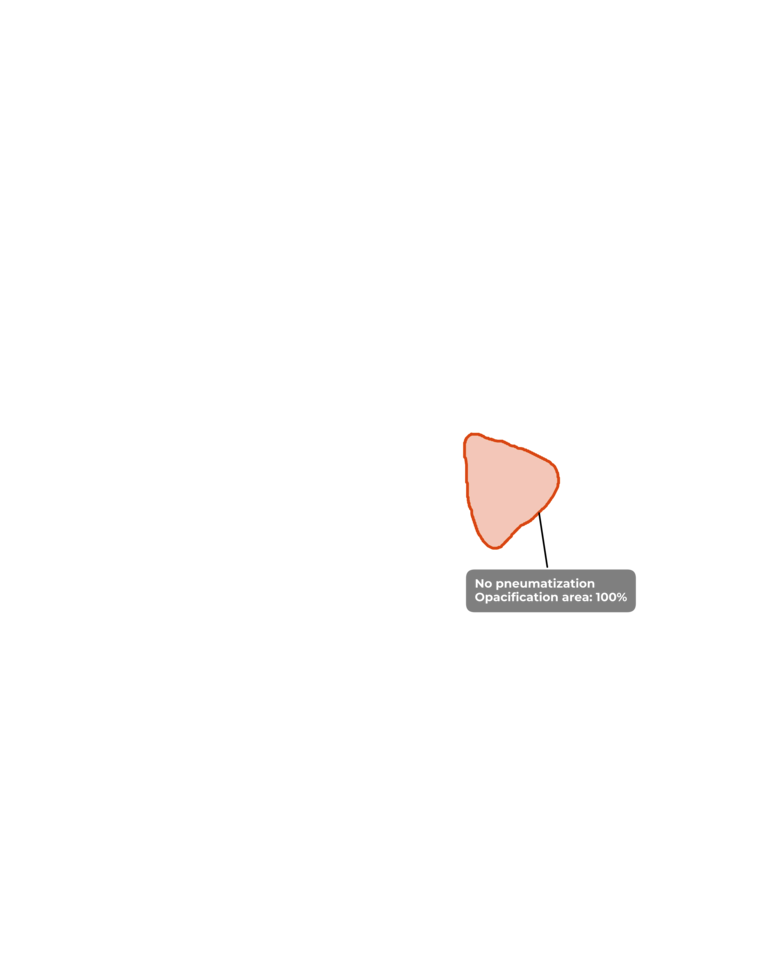

ИИ и умные алгоритмы для анализа рентгеновских снимков черепа. Обнаружение синусита и процента заполненности пазух носа менее чем за 30 секунд